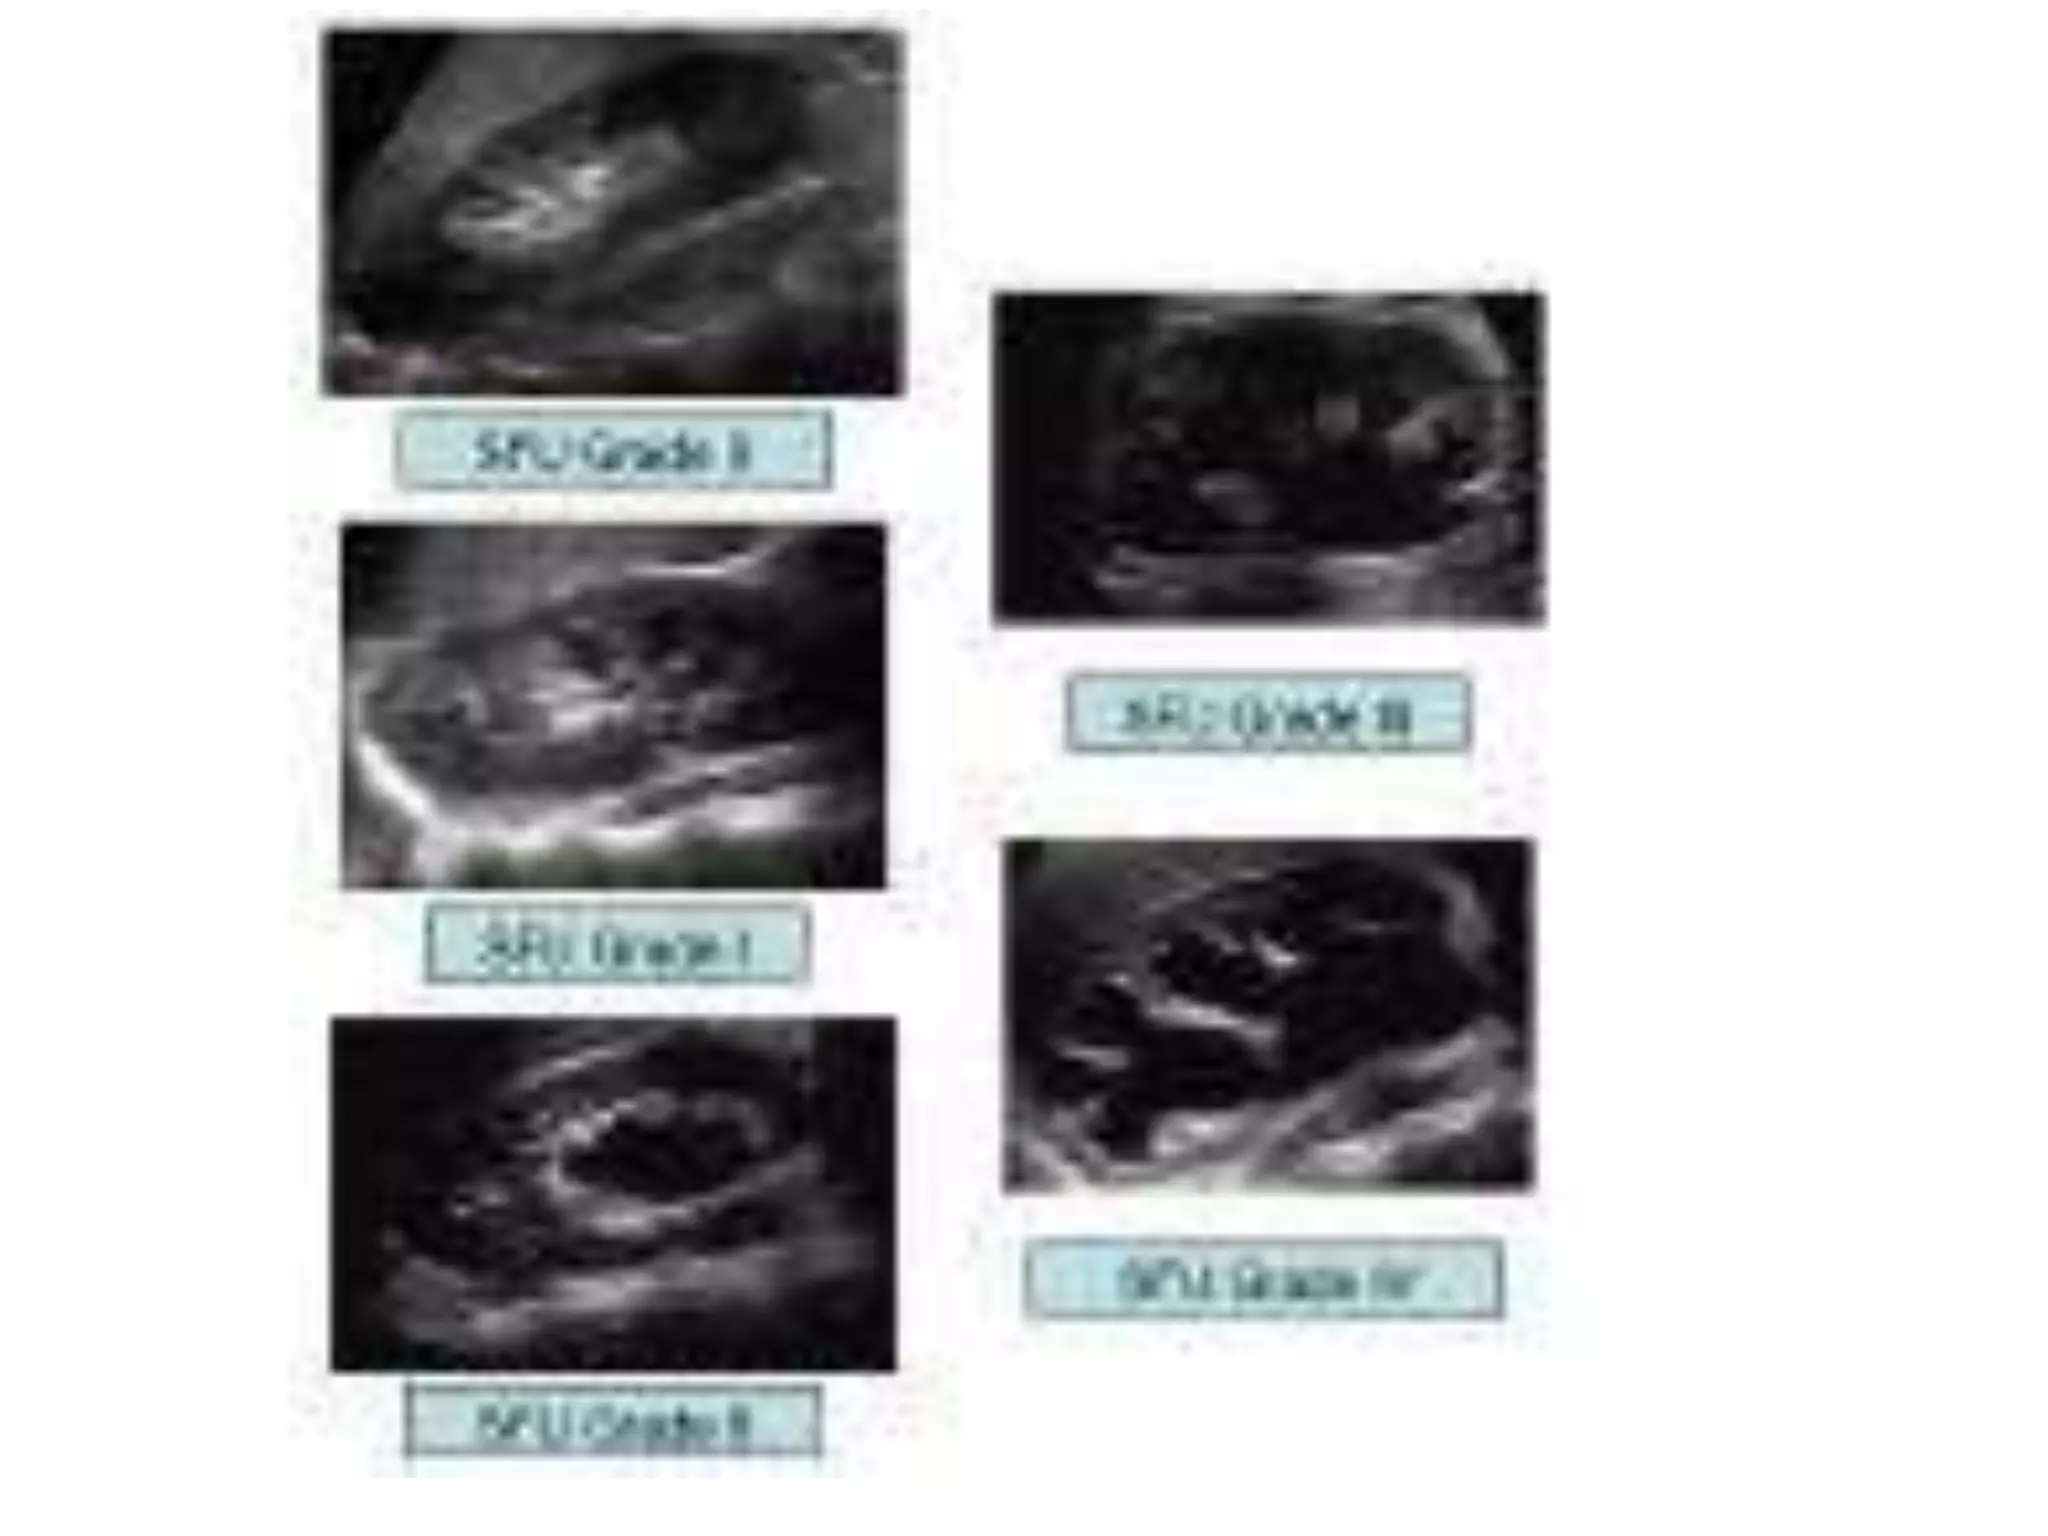

Clasificacion de la hidronefrosis

Grado 0: Riñón normal sin hidronefrosis

Grado 1: Pelvis renal ligeramente dilatada sin ectasia calicial

Grado 2: Pelvis renal moderadamente dilatada con ectasia calicial leve

Grado 3: Pelvis renal grande, cálices dilatados y parénquima normal

Grado 4: Pelvis renal muy grande, cálices grandes y dilatados

y adelgazamiento del parénquima renal.

Clasificacion de lahidronefrosis Grado 0: Riñón normal sin hidronefrosis Grado 1: Pelvis renal ligeramente dilatada sin ectasia calicial Grado 2: Pelvis renal moderadamente dilatada con ectasia calicial leve Grado 3: Pelvis renal grande, cálices dilatados y parénquima normal Grado 4: Pelvis renal muy grande, cálices grandes y dilatados y adelgazamiento del parénquima renal. • CLINICAS UROLOGICAS, MADRID ES.